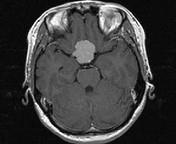

问题 女,32岁,右眼视物模糊1年,加重2月,请根据所提供图像,选择最可能的诊断()

选项 A.鞍区脑膜瘤 B.鞍区垂体瘤 C.鞍区转移瘤 D.鞍区海绵状血管瘤 E.鞍区动脉瘤

答案 A